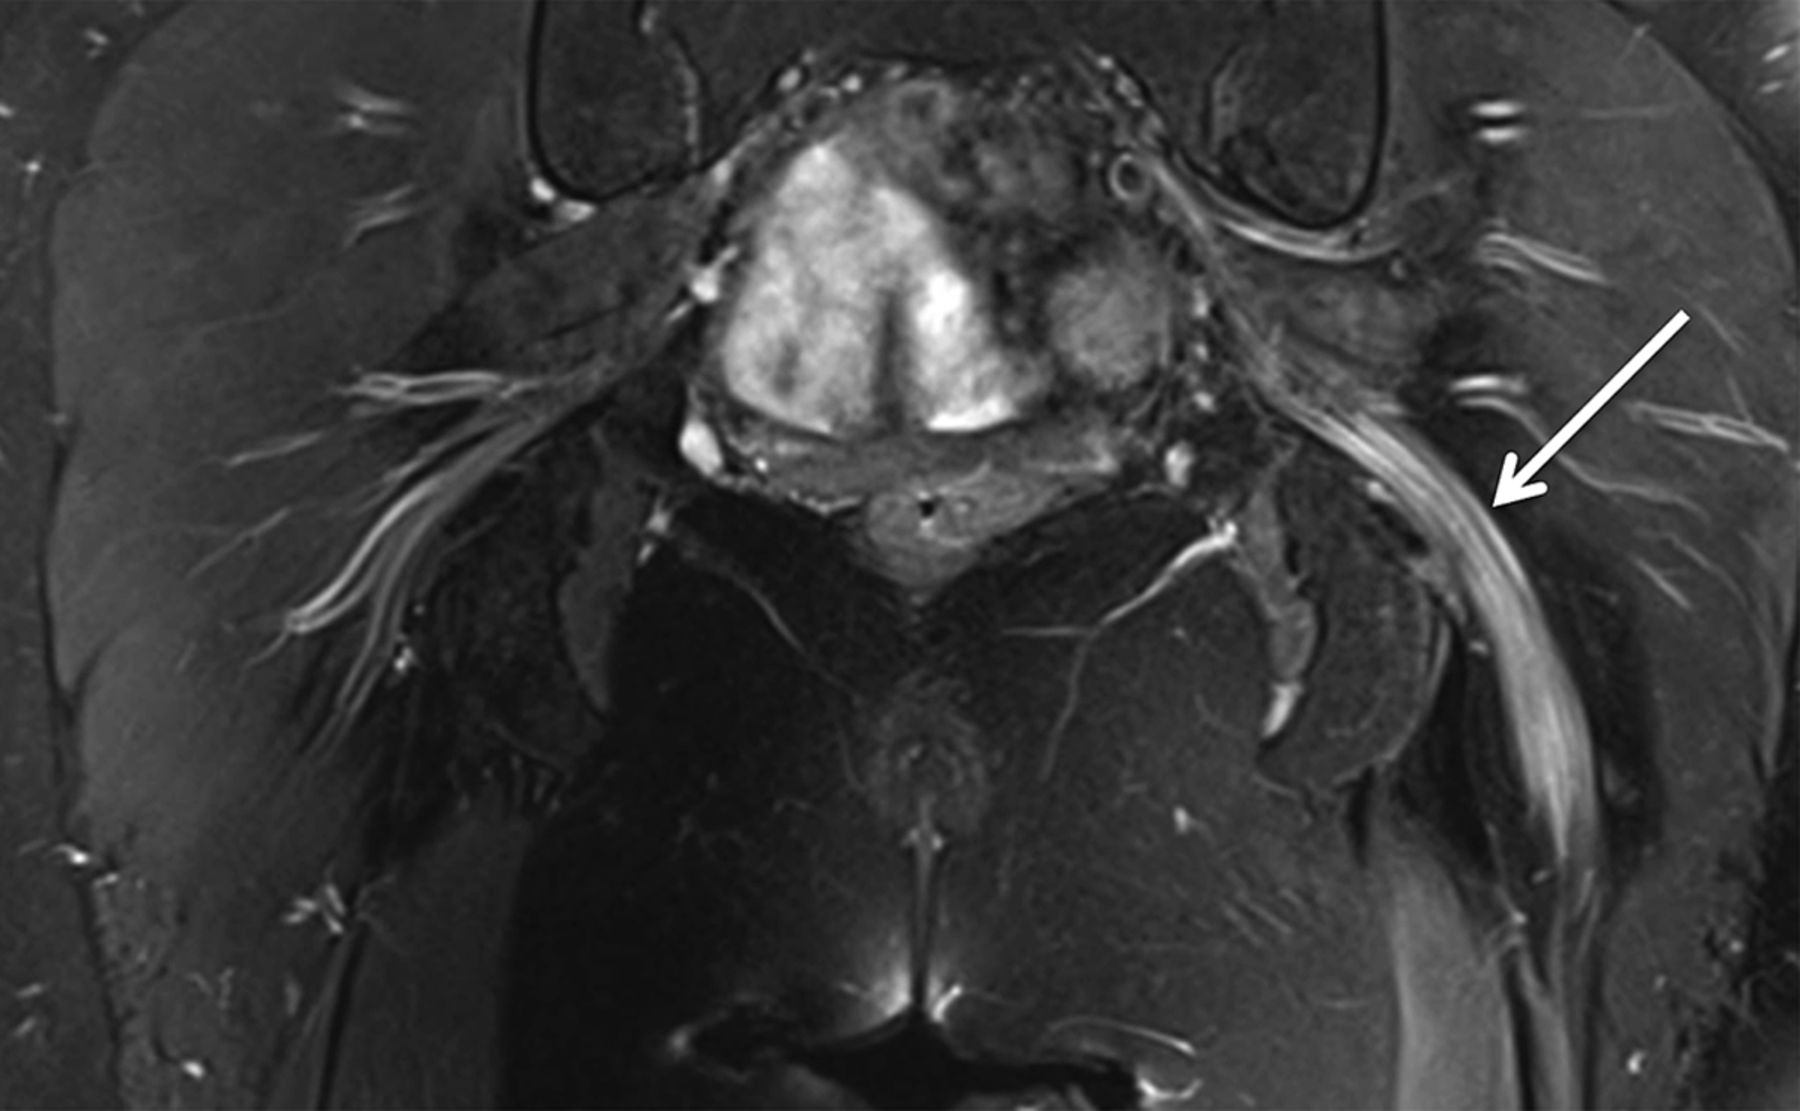

38岁的女人出现急性发作剧烈疼痛的吸海洛因后左小腿和脚。在考试,她远左下肢无力和足踝反射缺席。EMG在8周建议一个轴突坐骨神经病变。艾滋病毒检测是负面的。肌酸激酶、红细胞沉降率和c反应蛋白是正常的。MRI显示突出的水肿和扩大的左侧坐骨神经不对比度增强(图)。她收到了每周注入静脉甲基强的松龙导致改善她的症状和核磁共振的发现。公认的神经肌肉急性并发症海洛因使用包括单神经病,polyradiculoplexopathy,横纹肌溶解可能继发于炎症或毒性机制。1,2